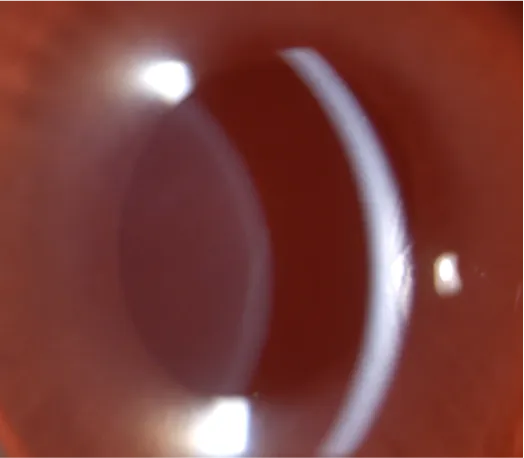

Tumor necrosis factor-alpha (TNF-α) is a key proinflammatory cytokine involved in inflammation. When administered intravitreally, TNF-α induces rapid infiltration of inflammatory cells in the anterior uvea and aqueous humor, mimicking features of acute uveitis. First demonstrated in rabbits by Rosenbaum et al. (1988) and further characterized by Fleisher et al. (1990), this model has since been widely used and validated as a reliable platform for studying ocular inflammation and testing anti-inflammatory therapies.

Clinical evaluation of uveitis severity is performed by an experienced veterinarian using slit-lamp biomicroscopy and scored according to the Modified Hackett-McDonald and the SPOTS (Semiquantitative Preclinical Ocular Toxicology Scoring) grading system.

Inflammation peaks on Day 7 and resolves by Day 14.